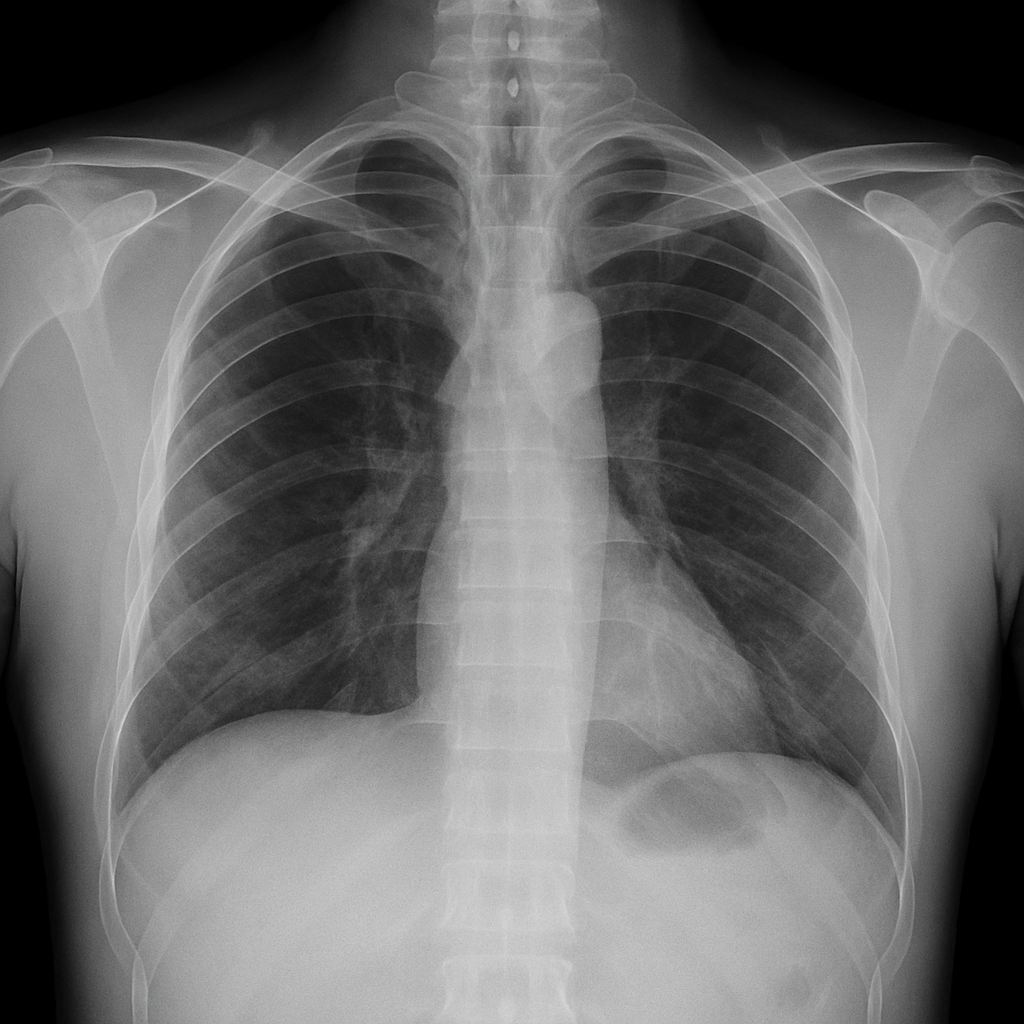

千葉市緑区 小渋医院 人間ドック レントゲン

胸部レントゲン(肺・心臓チェック)